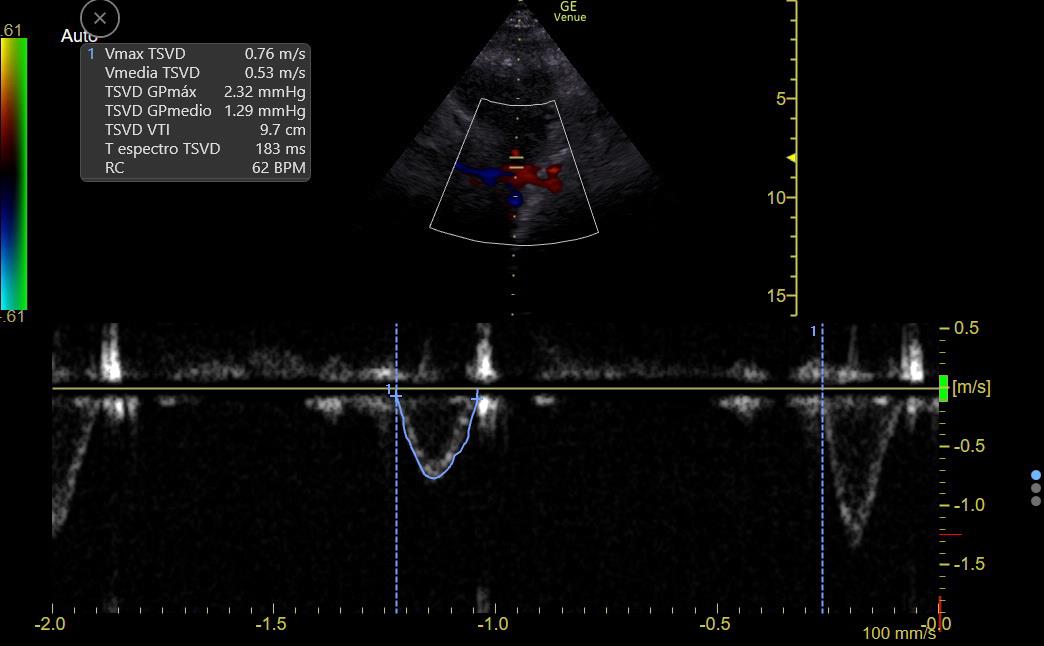

CO can be estimated by measuring flow at the LV or RV outflow tract:

RVOT Doppler shows ⬇️ VTI (9 to 14), so CO is LOW

There is ⬆️ respiratory variation: Low preload vs RV failure or Interdependence (Both Ruled out on #echofirst)

This suggests a low preload state

7/11